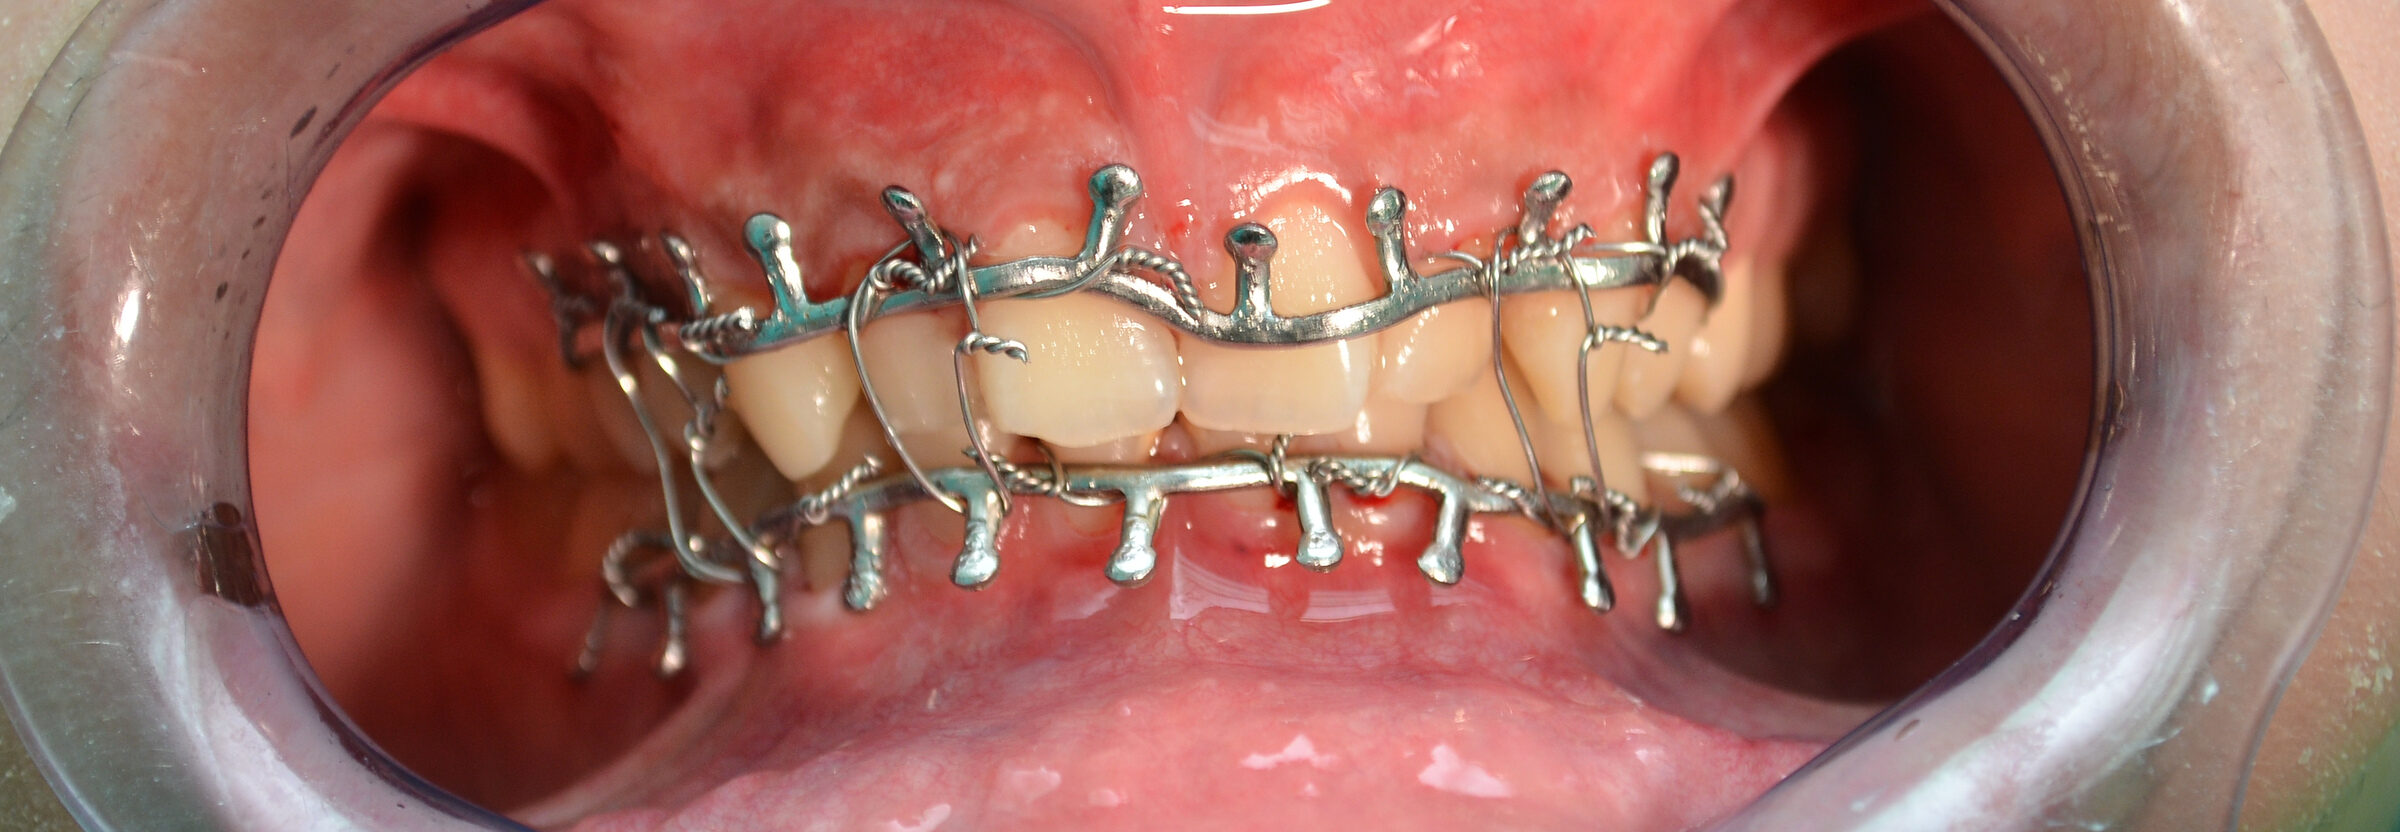

Treatment of broken jaws focuses on realigning and stabilizing the jawbone to ensure proper healing and restoration of function. A broken jaw, or mandibular fracture, is a common facial injury that can result from trauma such as falls, sports injuries, or vehicle accidents. Treatment often begins with a thorough assessment, including X-rays or CT scans, to determine the fracture’s severity and location. Methods of treatment can vary from wiring the jaws shut for minor fractures, allowing the bones to heal naturally while restricting movement, to surgical intervention for more severe cases.

Surgery may involve the use of plates, screws, and wires to secure the bones in the correct position. Post-treatment care includes a soft or liquid diet, pain management, and possibly antibiotics to prevent infection. Rehabilitation exercises may be necessary to restore full jaw function over time.

Treatment options range from non-surgical methods, like wiring the jaws shut for minor fractures, to surgical interventions using plates, screws, and wires to secure the bones for more severe fractures.